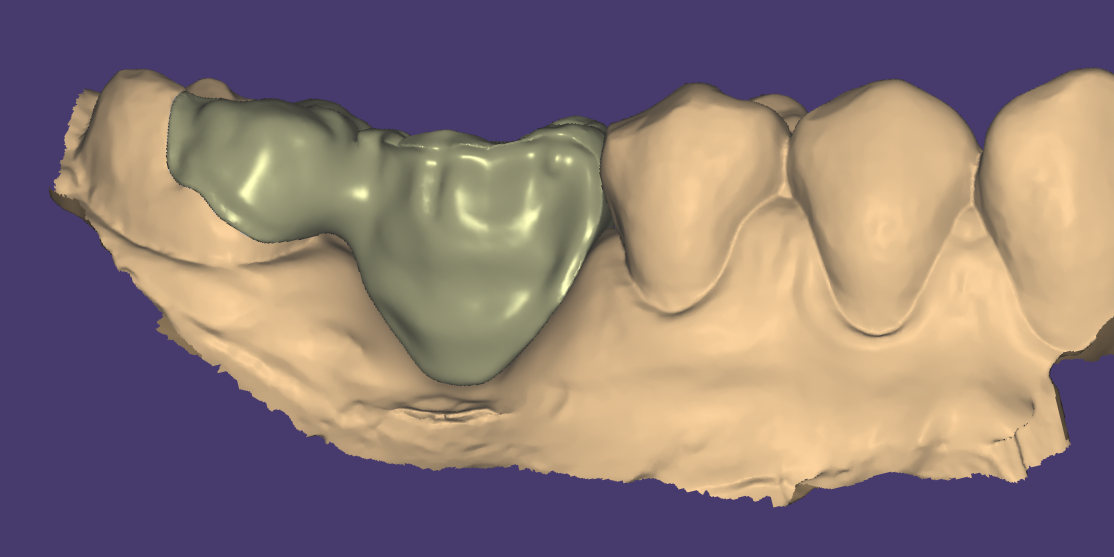

Relativement récents, les bridges collés cantilever postérieurs constituent une alternative fixe, fiable et véritablement minimalement invasive aux implants dans les secteurs postérieurs. Cette thérapeutique qui repose sur des indications bien précises est parfois débattue avec passion sur les réseaux sociaux ou dans les congrès scientifiques. Cependant des études cliniques existent, tout comme des recommandations validées dans des journaux internationaux. Leur succès repose sur des préparations et des principes biomécaniques rigoureux, pourtant simples à intégrer au quotidien. Cette intervention propose un guide clair et opérationnel incluant indications, étapes clés, protocoles d’adhésion et réglages occlusaux pour les mettre en œuvre avec confiance et reproductibilité.